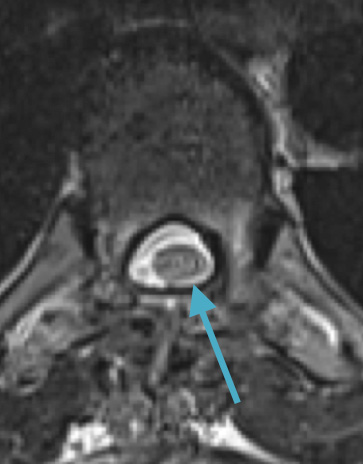

Preoperative MRI T1w demonstrating a large enhancing tumor with severe cord compression

This is a 55-year-old female with no past medical history who presented electively with a 10 month history of progressively worsening mid back pain radiating across the chest, and gait disturbance. Pain was especially worse at night and when laying flat. Her exam was pertinent for severe ataxia when ambulating, and elevated deep tendon reflexes in the lower extremities. She had severe and debilitating symptoms, as demonstrated by her Visual Analog Scale (VAS) and Oswestry Disability Index (ODI) of 9/10 and 64/100, respectively. MRI of the thoracic spine with and without contrast demonstrated a large intradural extramedullary homogenously enhancing mass at T8, resulting in near obliteration of the spinal canal and severe cord compression. She was referred to Dr. Xavier Gaudin for neurosurgical management.